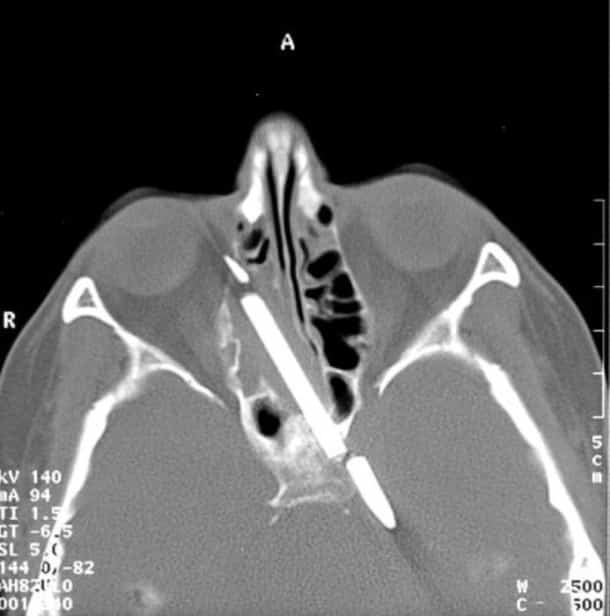

33 radiographies qui prouvent que les gens font des choses douteuses avec leur corps !